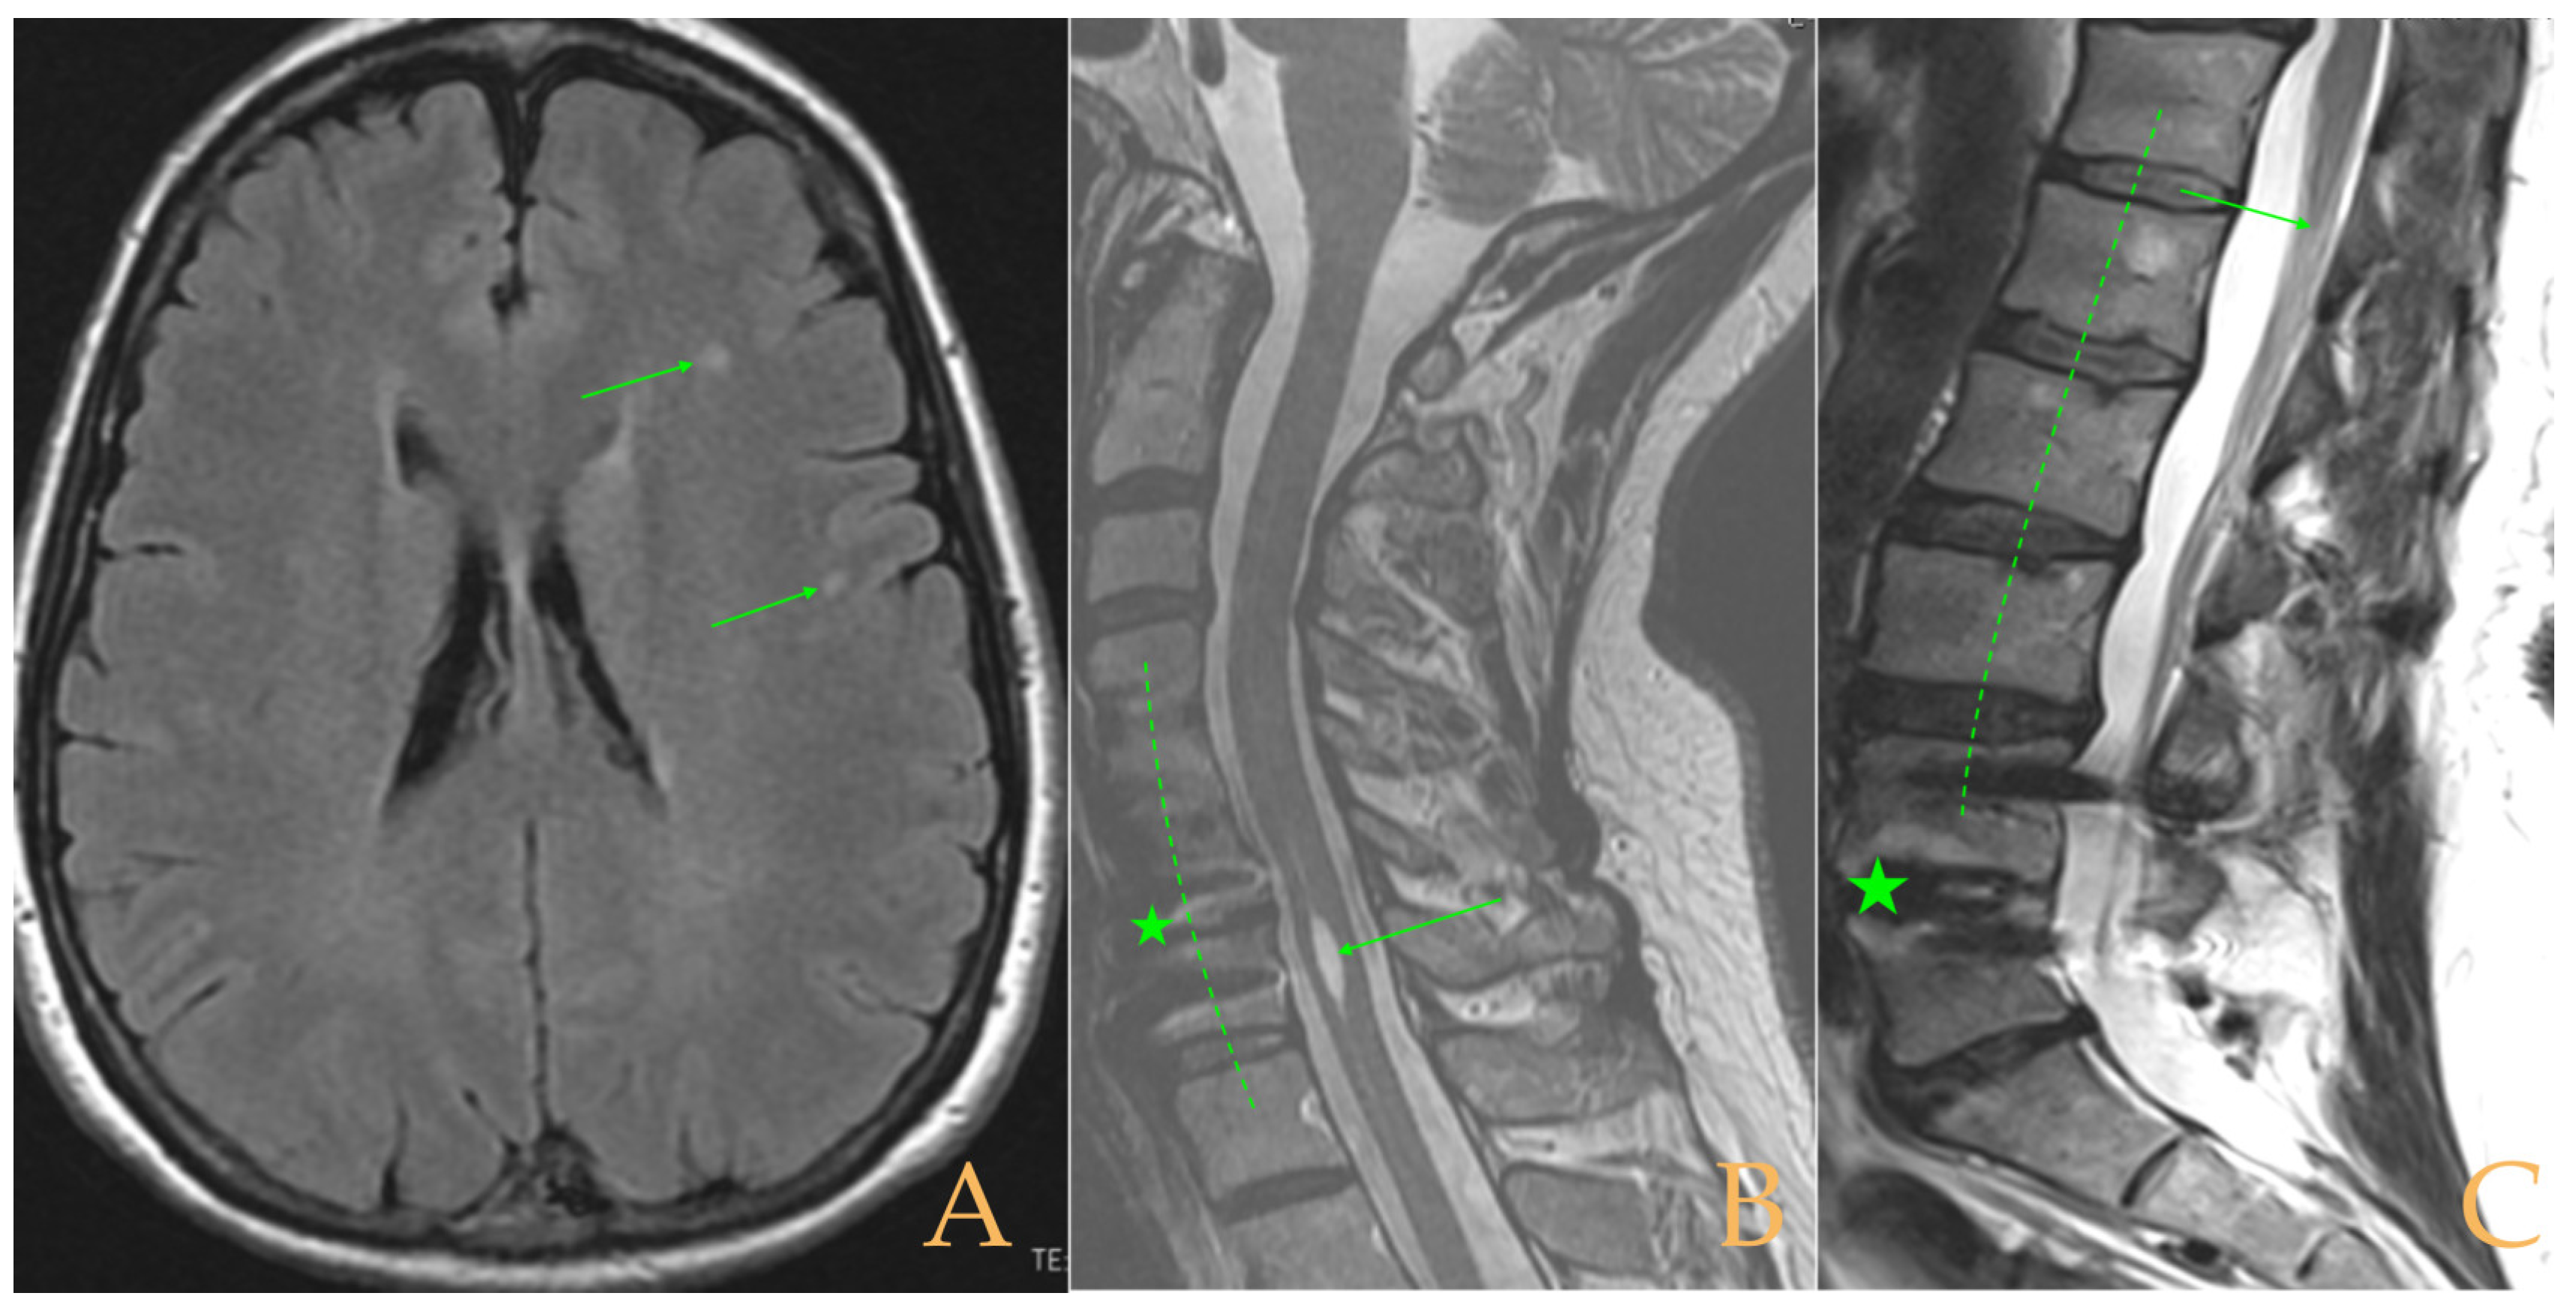

The MRI showed (Figure 9): descent of the cerebellar tonsils, ischemic foci in the white matter of the cerebral hemispheres, and oedema in the optic nerve sheaths. Kyphosis of the cervical spine (especially C5-C6-C7). Tense aspect of the cervical spinal cord. Disc disease: C3-C4-C5-C6-C7-T1. Ischemia and cervical and thoracic oedema. Straightening and scoliosis of the thoracic spine. Lumbar lordosis straightening. Conus medullaris at the level of the middle third of L1. Postsurgical changes in L4-L5 (disc prosthesis). The full-spine X-rays showed cervical, thoracic, and lumbar scoliosis, with the biggest curve being dextroconvex of wide radius in the thoracic and lumbar region.

Figure 9.

Imaging of patient 9. A: MRI of the posterior fossa, descent of the cerebellar tonsils (arrow), and increased supracerebellar space (star); B: straightening of the cervical spine (interrupted line) and suboccipital craniectomy with C1 laminectomy (star); and C: conus medullaris at the level of the middle third of L1 (arrow) and L4L5 disc prosthesis (star).